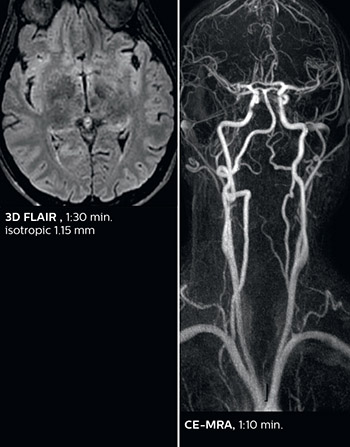

Comprehensive stroke MRI within acceptable time

Dr. Savatovsky appreciates the improvements and flexibility that Elition with Compressed SENSE and MultiBand SENSE provides, particularly for stroke patients. “For stroke, it allows us to cut about 5 minutes off of our stroke protocol, or to keep the same acquisition time and get more insights.”

The ability to perform more sequences can help in making a swift and confident diagnosis. “For example, our stroke cases usually include the regular sequences that every center does (b1000 diffusion, FLAIR, time-of-flight angiography), but we also image supra aortic vessels, and we can replace a gradient echo sequence with a fast 50-second susceptibility-weighted sequence, and all of this doesn’t add much time. because all the regular sequences are accelerated on Elition.”

Fast acute stroke protocol

This is an example of acute ischemic stroke with distal occlusion of the right posterior cerebral artery. Note the improved visibility of the ischemic territory on the diffusion weighted image with high b-value. The 3D FLAIR shows a distal PCA occlusion. The fast SWIp depicts the thrombus on the isolated second echo image. The total scan time (including SmartBrain, preparations and a fast 3D T1w TSE Gd) is 8:00 minutes.